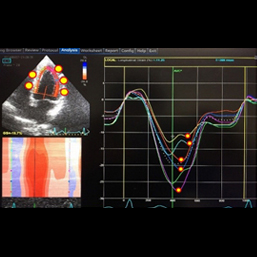

ところが、当院のスペックルトラッキング法、心臓超音波機器を用いることにより、24時間~48時間前の発作をまるでタイムマシンのように追跡することができるケースも出てくるようになりました。

開業以来、複数名の方が当院で診断を得られています。その診断に基づいた治療により、症状も劇的に改善しています。この医療機器を用いても保険診療ですので、患者様のご負担は他のエコー機器の場合と同様です。心電図に変化がなくても、急性心筋梗塞を発見し得たケースもあります。この最新の超音波機器が当院の特徴です。

1.撮影

2.撮影したエコーを解析